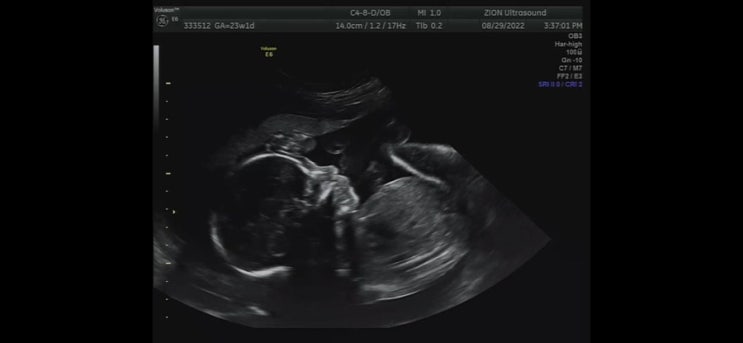

[임신기록] (3) 임신 중기